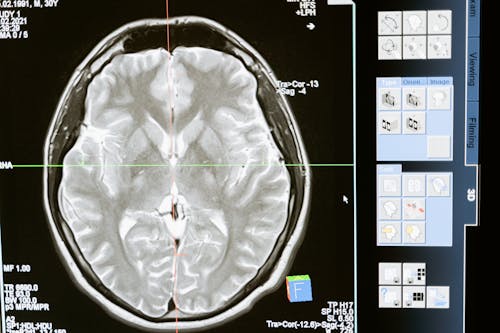

뇌의 활동을 관찰할 수 있는 현대 기술, 예를 들어 fMRI(기능성 자기공명영상법)와 PET(양전자방출단층촬영)은 뇌가 대부분의 시간 동안 매우 활발하게 활동하고 있음을 보여줍니다. 단순한 휴식 상태에서도 뇌는 전반적으로 활성화된 상태를 유지합니다. 이 때도 우리가 생각하고 느끼고, 심지어 잠을 잘 때도 여러 신경 네트워크가 활발하게 작동하고 있습니다.